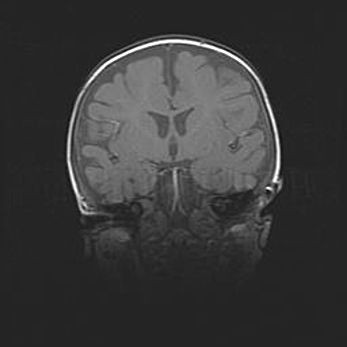

Лейкомаляция с кистозно-глиозной дегенерацией головного мозга.

Возраст: 2 месяца 25 дней

Вес: 6400 г

Окружность головы: 40 см

Срок гестации: 41 неделя

Лейкомаляцию относят к ишемически-гипоксическим повреждениям головного мозга, диагностируемым у новорожденных. При лейкомаляции в головном мозге обнаруживают очаги некроза, возникшие после тяжелой гипоксии и нарушения кровотока. В процессе морфогенеза очаги проходят три стадии: 1) развития некроза, 2) резорбции и 3) формирования глиозного рубца или кисты. Перивентрикулярная лейкомаляция (ПЛ) встречается примерно в 12% случаев среди новорожденных, обычно – у недоношенных детей, причем, частота ее зависит от массы, с которой младенец появился на свет. Наибольшее число малышей страдает лейкомаляцией, если масса при рождении 1500-2500 г.